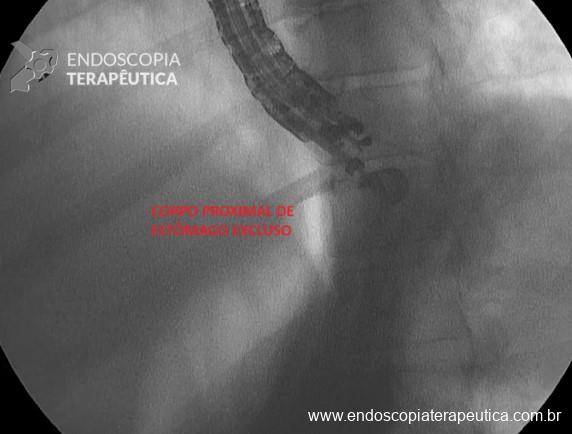

- Retrair a agulha e reposicionar o ecoendoscópico até visualizar a parte proximal do corpo gástrico excluso, logo abaixo da transição esogagogástrica, confirmando com ecoendoscopia, visão endoscópica e fluoroscopia;

- Repuncionar com FNA 19G, em corpo proximal e distender o estômago excluso novamente com soro fisiológico em bomba até ter uma janela de punção com lúmen de ao menos 3 cm e visualizar o contraste em fundo (Figura 5);

- Disparo do LAMS (preferencialmente de 20 mm de diâmetro) em corpo proximal do estômago excluso o mais distal à transição esofagogástrica e proximal à anastomose gastrojejunal (Figura 6);